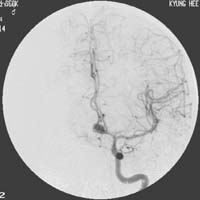

<³úÁöÁÖ¸·ÇÏÃâÇ÷>

<¼ö¼ú

Àü>

³úµ¿¸Æ·ù¿¡

ÀÇÇÑ ÁöÁÖ¸·ÇÏÃâÇ÷ÀÇ CT¼Ò°ß ¹× Ç÷°üÁ¶¿µ¼ú¿¡¼

Àü±³Å뵿¸Æ¿¡ µ¿¸Æ·ù°¡ º¸À̰í ÀÖ´Ù.

Àå¸é> <¼ö¼ú

ÈÄ>

¼ö¼ú

ÈÄ µ¿¸Æ·ù°¡ º¸ÀÌÁö ¾ÊÀ¸¸ç µ¿¸Æ·ù °æºÎ¿¡

Ŭ¸³ÀÌ µé¾î°¡ ÀÖ´Â °ÍÀÌ º¸À̰í

ÀÖ´Ù.

<³úÁ¤µ¿¸Æ±âÇü>

½Ã»óµ¿

ÀÎÁ¢ºÎ ºÎÀ§ÀÇ ³úÁ¤µ¿¸Æ±âÇüÀÇ MRI¿Í Ç÷°üÁ¶¿µ¼ú

¼Ò°ß

<¸ð¾ß¸ð¾ßº´(¼Ò¾ÆÁßdz)>

¿ìÃø

³»°æµ¿¸ÆÀÇ Æó»ö¼Ò°ß°ú °æµ¿¸ÆºÎÀ§ÀÇ

ÀÌ»óÇ÷°ü¸Á ¼Ò°ßÀÌ º¸À̰í ÀÖ´Ù. |